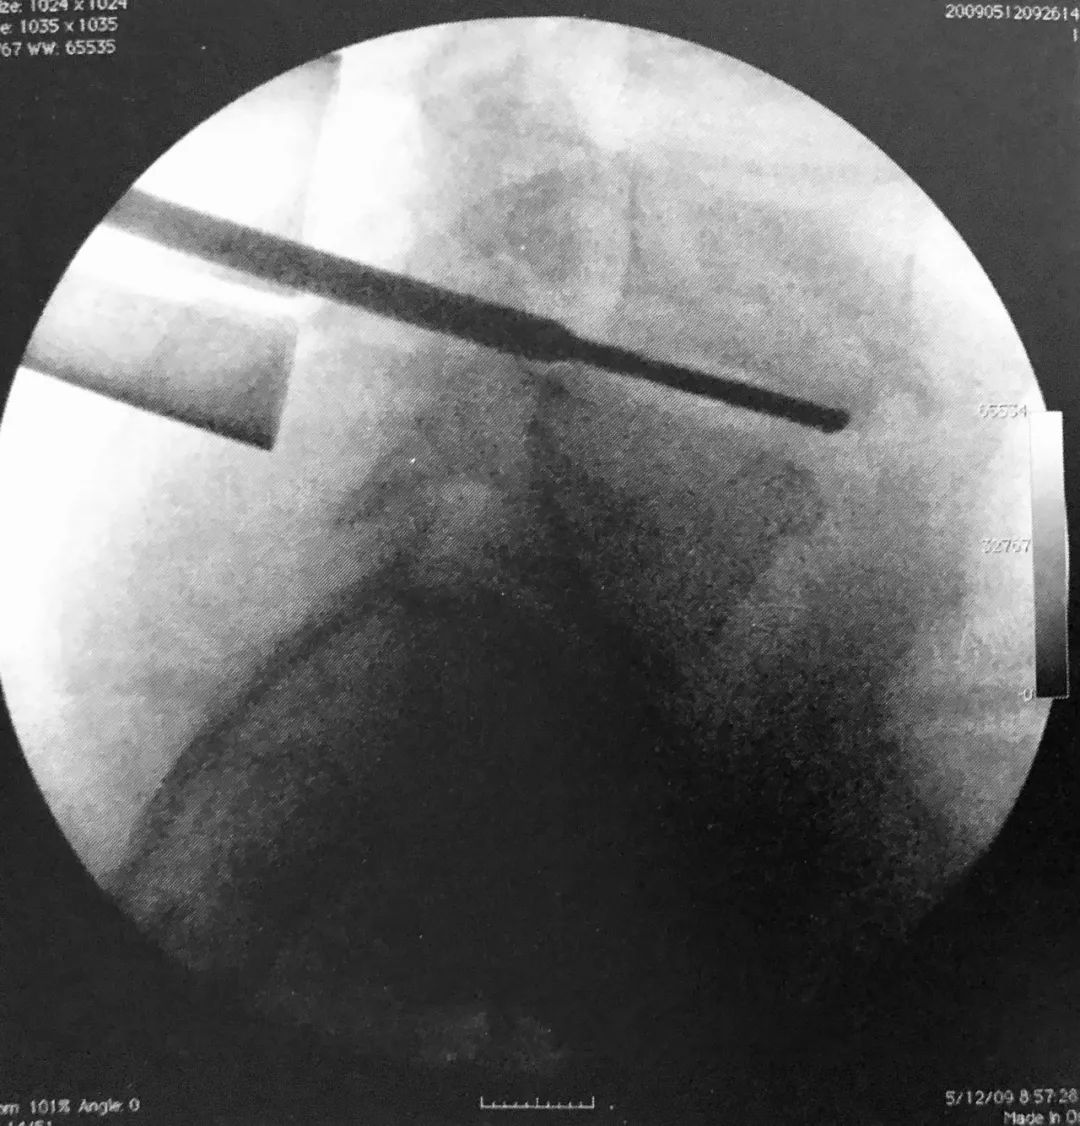

3. 球囊套管的开口点应位于椎弓根的 10 点或 2 点位置即上外侧角,取决于左右。将置入通道设计于该处可保证其离神经根最远。如前后位片所示插入通道,侧位片上套管通过椎体后缘线之前不能越过椎弓根内壁。

5. 术中透视证实球囊位于椎体前部,这可避免骨折块向后突入椎管。

7. 透视下向椎体内注入骨水泥,在正侧位片上仔细观察以确保椎体边缘不被侵犯。如果发现骨水泥溢出,则停止注入。应避免将骨水泥注入椎体后部。

8. 理想情况下,正位片上骨水泥充填应该通过中线。